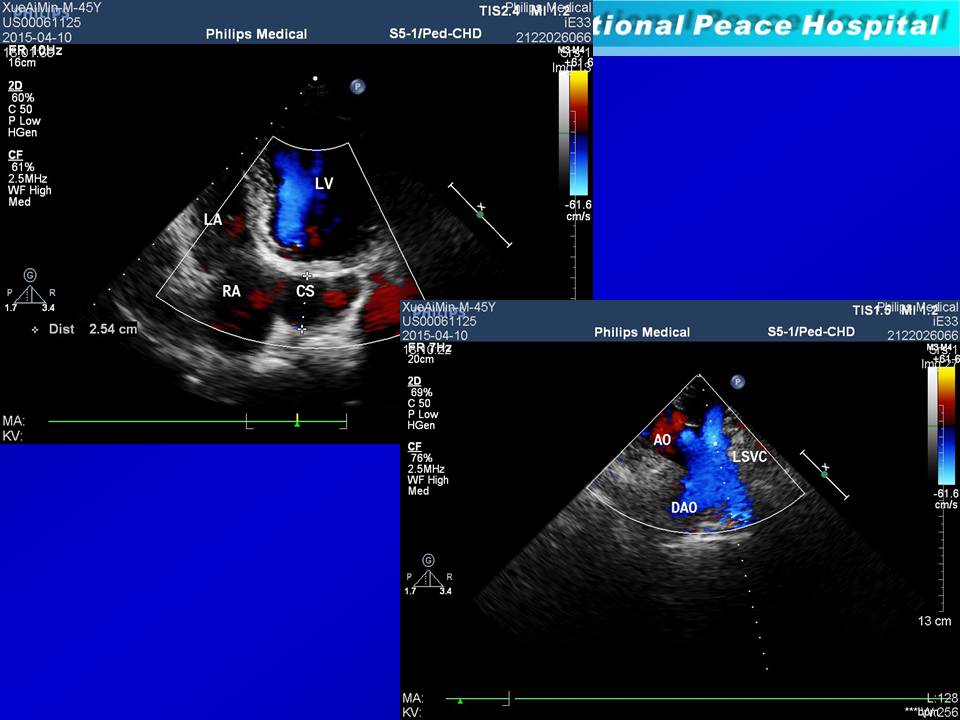

静脉畸形合并房室结折返性心动过速 射频消融1例

丁超 齐书英